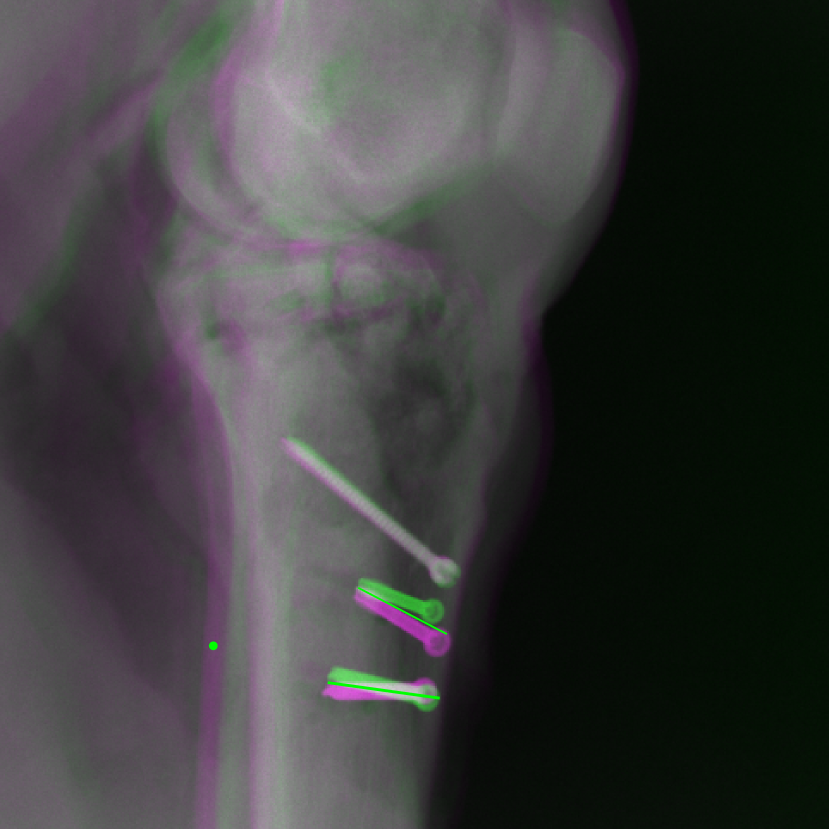

Figure 14: The results for the real cadaver leg data. The green dots mark the positions of landmarks in the corresponding reference images. In the first column, the arrows indicate the bone cavity/fracture structures. In the second column, the solid lines mark the widths and heights of the metals. The green ones are measured from the DRR reference, while the red ones are measured in the corresponding perspective projection image. In the last column, the lines mark the centerlines of the metal screws, where the green lines are those from the reference image. The lengths of the lines in mm are displayed in their corresponding subcaptions. Intensity window: [0, 4]. Please zoom in for better visualization.

The complementary view setting for learning perspective deformation is also evaluated on real CBCT projection data. In this evaluation, real CBCT projection data from a dataset of knees with metal implants is used for testing, while DRRs created from volumetric CT datasets with inserted metals is used for training. Three exemplary DRR perspective projection images for training are displayed in Fig. 13, in which synthetic metal implants are inserted [34]. The appearance, e.g., image contrast and metal image resolution, of such DRR training images is different from that of real projection images in Fig. 14. In Fig. 14, the results for three knees, with and without metal implants, are displayed. The first and second rows are the 0superscript00^{\circ} and 180superscript180180^{\circ} perspective projections, respectively, rebinned to the virtual detector with geometric calibration based on their respective principal points and projections of the world origin. The third row displays their difference images, where the magnitude of deviation increases from the center towards the outside like it does in DRRs with an ideal scan trajectory (e.g., Fig. 6(e)), although real projection data suffer from various physical effects like beam hardening and Poisson noise. The fourth row displays the RGB stacks of 0superscript00^{\circ} and 180superscript180180^{\circ} perspective projection images. The magenta and green regions indicate structures with considerable perspective deformation, for example, the knee patella in Fig. 5.4, the top parts of the two metals in Fig. 5.4, and the bottom two screws in Fig. 5.4. The fifth row displays reference images, which are orthogonal projections of iterative reconstruction volumes from measured CBCT projection data. In the reference images, a total of five landmarks are selected, with the positions being marked by the green dots: In Fig. 5.4, two positions at the edges of the knee patella are marked; In Fig. 14(e) and Fig. 14(f), one position at the left edge of the fibula is marked for each image. In addition, a rectangular frame for the two metals is marked by the green dashed lines, while its width and height are indicated by the green solid lines, which are 29.71 mm and 111.99 mm, respectively. In Fig. 14(f), the centerlines of the bottom two screws are sketched by the green lines, which have the lengths of 17.14 mm (middle screw) and 19.38 mm (bottom screw). The corresponding rectangular frame for the two metals and the screw centerlines in the perspective projection images are marked as well, but in red color. In Fig. 14(a), the width and height of the metals are 32.56 mm and 109.85 mm, which have deviations of 2.84 mm and -1.95 mm to the reference ones, respectively. In Fig. 14(b), the centerline lengths are 18.91 mm and 19.54 mm, which have deviations of 1.77 mm and 0.16 mm, respectively. Although the bottom screw has little length deviation to the reference, the orientations of both screws are obviously deviated. The sixth row shows the results of Pix2pixGAN using 0superscript00^{\circ} and 180superscript180180^{\circ} polar inputs. For all of the landmarks, the green reference dots are all located accurately in the Pix2pixGAN images. The rectangular reference frame also accurately covers the metals in Fig. 14(g). In Fig. 14(h), although the two red centerlines do not exactly overlap with the green one, they are very close in lengths and orientations. Please zoom in for better visualization.

The region-of-interest covering the cavity/fracture structures indicated by the red arrow in Fig. 14 has been enlarged in Fig. 15 for better visualization of image resolution. In the real 0superscript00^{\circ} perspective projection ROI (Fig. 15(a)), the cavities and bone edges appear sharp. The presence of Poisson noise can also be visualized to some degree. In the DRR reference ROI (Fig. 15(b)), the cavities and bone edges appear blurry. This is likely caused by the partial volume effect in the intermediate 3D reconstruction volumes. In the Pix2pixGAN output (Fig. 15(c)), there is a slight smoothing effect. For example, the fine edge indicated by the arrow is blurred and the Poisson noise is reduced. But in general, image resolution is preserved for most anatomical structures, e.g., the cavities.